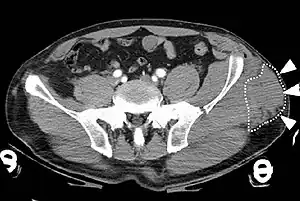

| A Morel-Lavallée lesion involving the left pelvis as seen on CT scan. | |

Diagnosis is based on examination and may be supported by medical imaging.[2] MRI or ultrasound are particularly useful.[3] On CT scan a MLL has lower Hounsfield units than a hematoma (17 versus 75).[1]